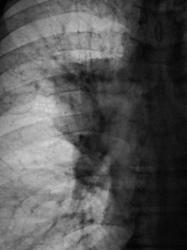

деформация правого корня. Он смещён немного вверх. Картина похоже на течение онкопроцесса.

Новообразование в области правого верхнедолевого бронха, центральная форма, ателектаз или обструктивный пневмонит в третьем сегменте, лимфангит во всей доле, расширение вехнего средостения вправо - метастазы?

Валентин Львович, а Вы не хотите сделать боковую томограмму через тень (корень) и томограмму на правый в/долевой бронх. Потому как ни одной из томограмм ни тень, ни бронхи справа не в срезе, а есть у меня такое впечатление, что имеет место периферический узел в S3, проекционно накладывающийся на тень корня, кроме того, при таком конгломерате в корне, должна быть более выражена гиповентиляция...